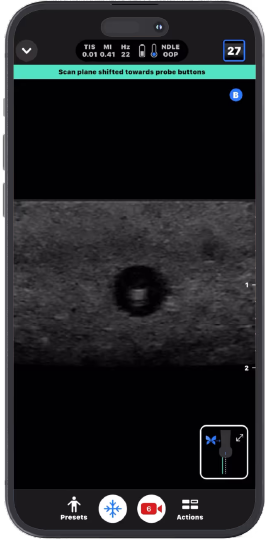

Agulha: Fora do Plano™

Uma predefinição projetada para visualização mais precoce da ponta da agulha, a 1 mm do ponto de entrada, permitindo procedimentos mais bem-sucedidos.